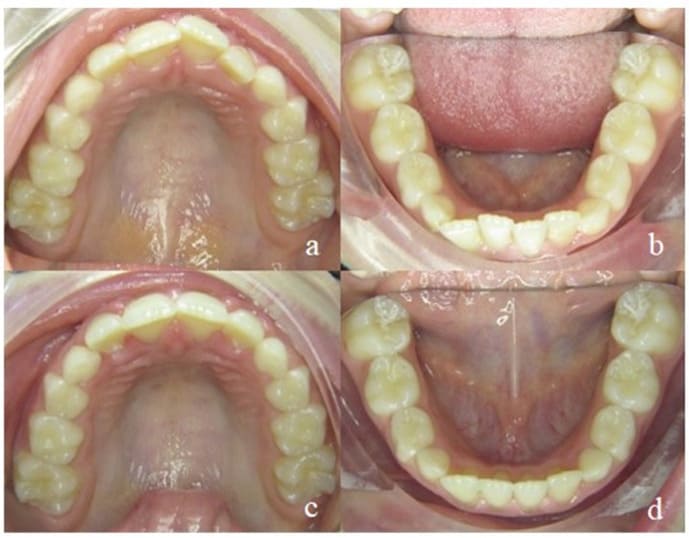

Additionally, their function as an orthodontic appliance is surprisingly beneficial and has been shown by Keski-Nisula [12]. In 5-year-old children statistically significant improvements in terms of molar relationship, overjet, overbite, incisor alignment and mandibular growth enhancement can be achieved after three years of treatment compared to a control group, even without any additional myofunctional training and exclusive nighttime ware [13]. Furthermore, these results proved to be stable 11 years posttreatment [13]. In growing patients, teeth (and jaws) are guided by very mild pressure into the space provided by the EGA which act like a set-up or the final aligner in a treatment plan. Thus, the choice of the correct EGA for the respective malocclusion is crucial to allow an effective treatment. Figure 3 shows the alignment that can be achieved with one EGA after 6 months only.

Figure 3: Alignment of the upper (a, c) and lower (b, d) jaw after 6 months of EGA-treatment.